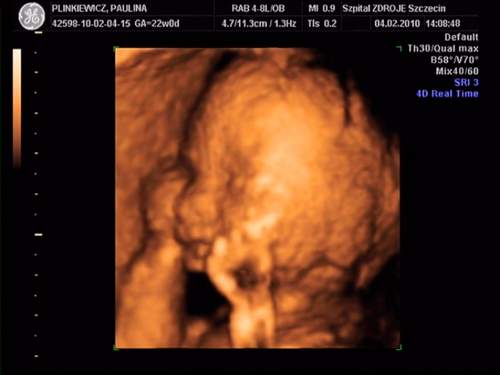

MAleńka jest super....Rozumiem że to imienniczka mojej córci - Pola!!!! Jest cudowna...Gratuluję!!!!Moja córeczka:

na drugim zdjęciu ziewa :-) a na ostatnim trzyma się za uszko:-)